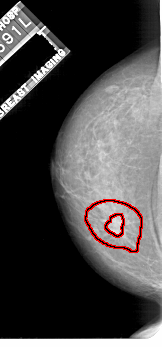

FILE: A_1112_1.LEFT_CC.OVERLAY

TOTAL_ABNORMALITIES 1

ABNORMALITY 1

LESION_TYPE MASS SHAPE IRREGULAR MARGINS SPICULATED

ASSESSMENT 5

SUBTLETY 5

PATHOLOGY MALIGNANT

TOTAL_OUTLINES 2

BOUNDARY

CORE